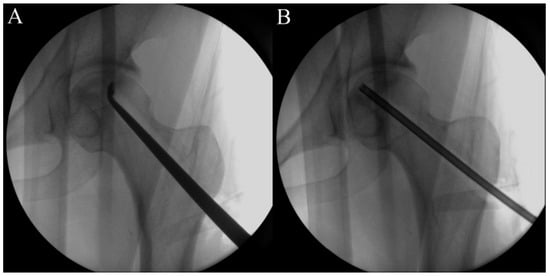

2.5. Procedure